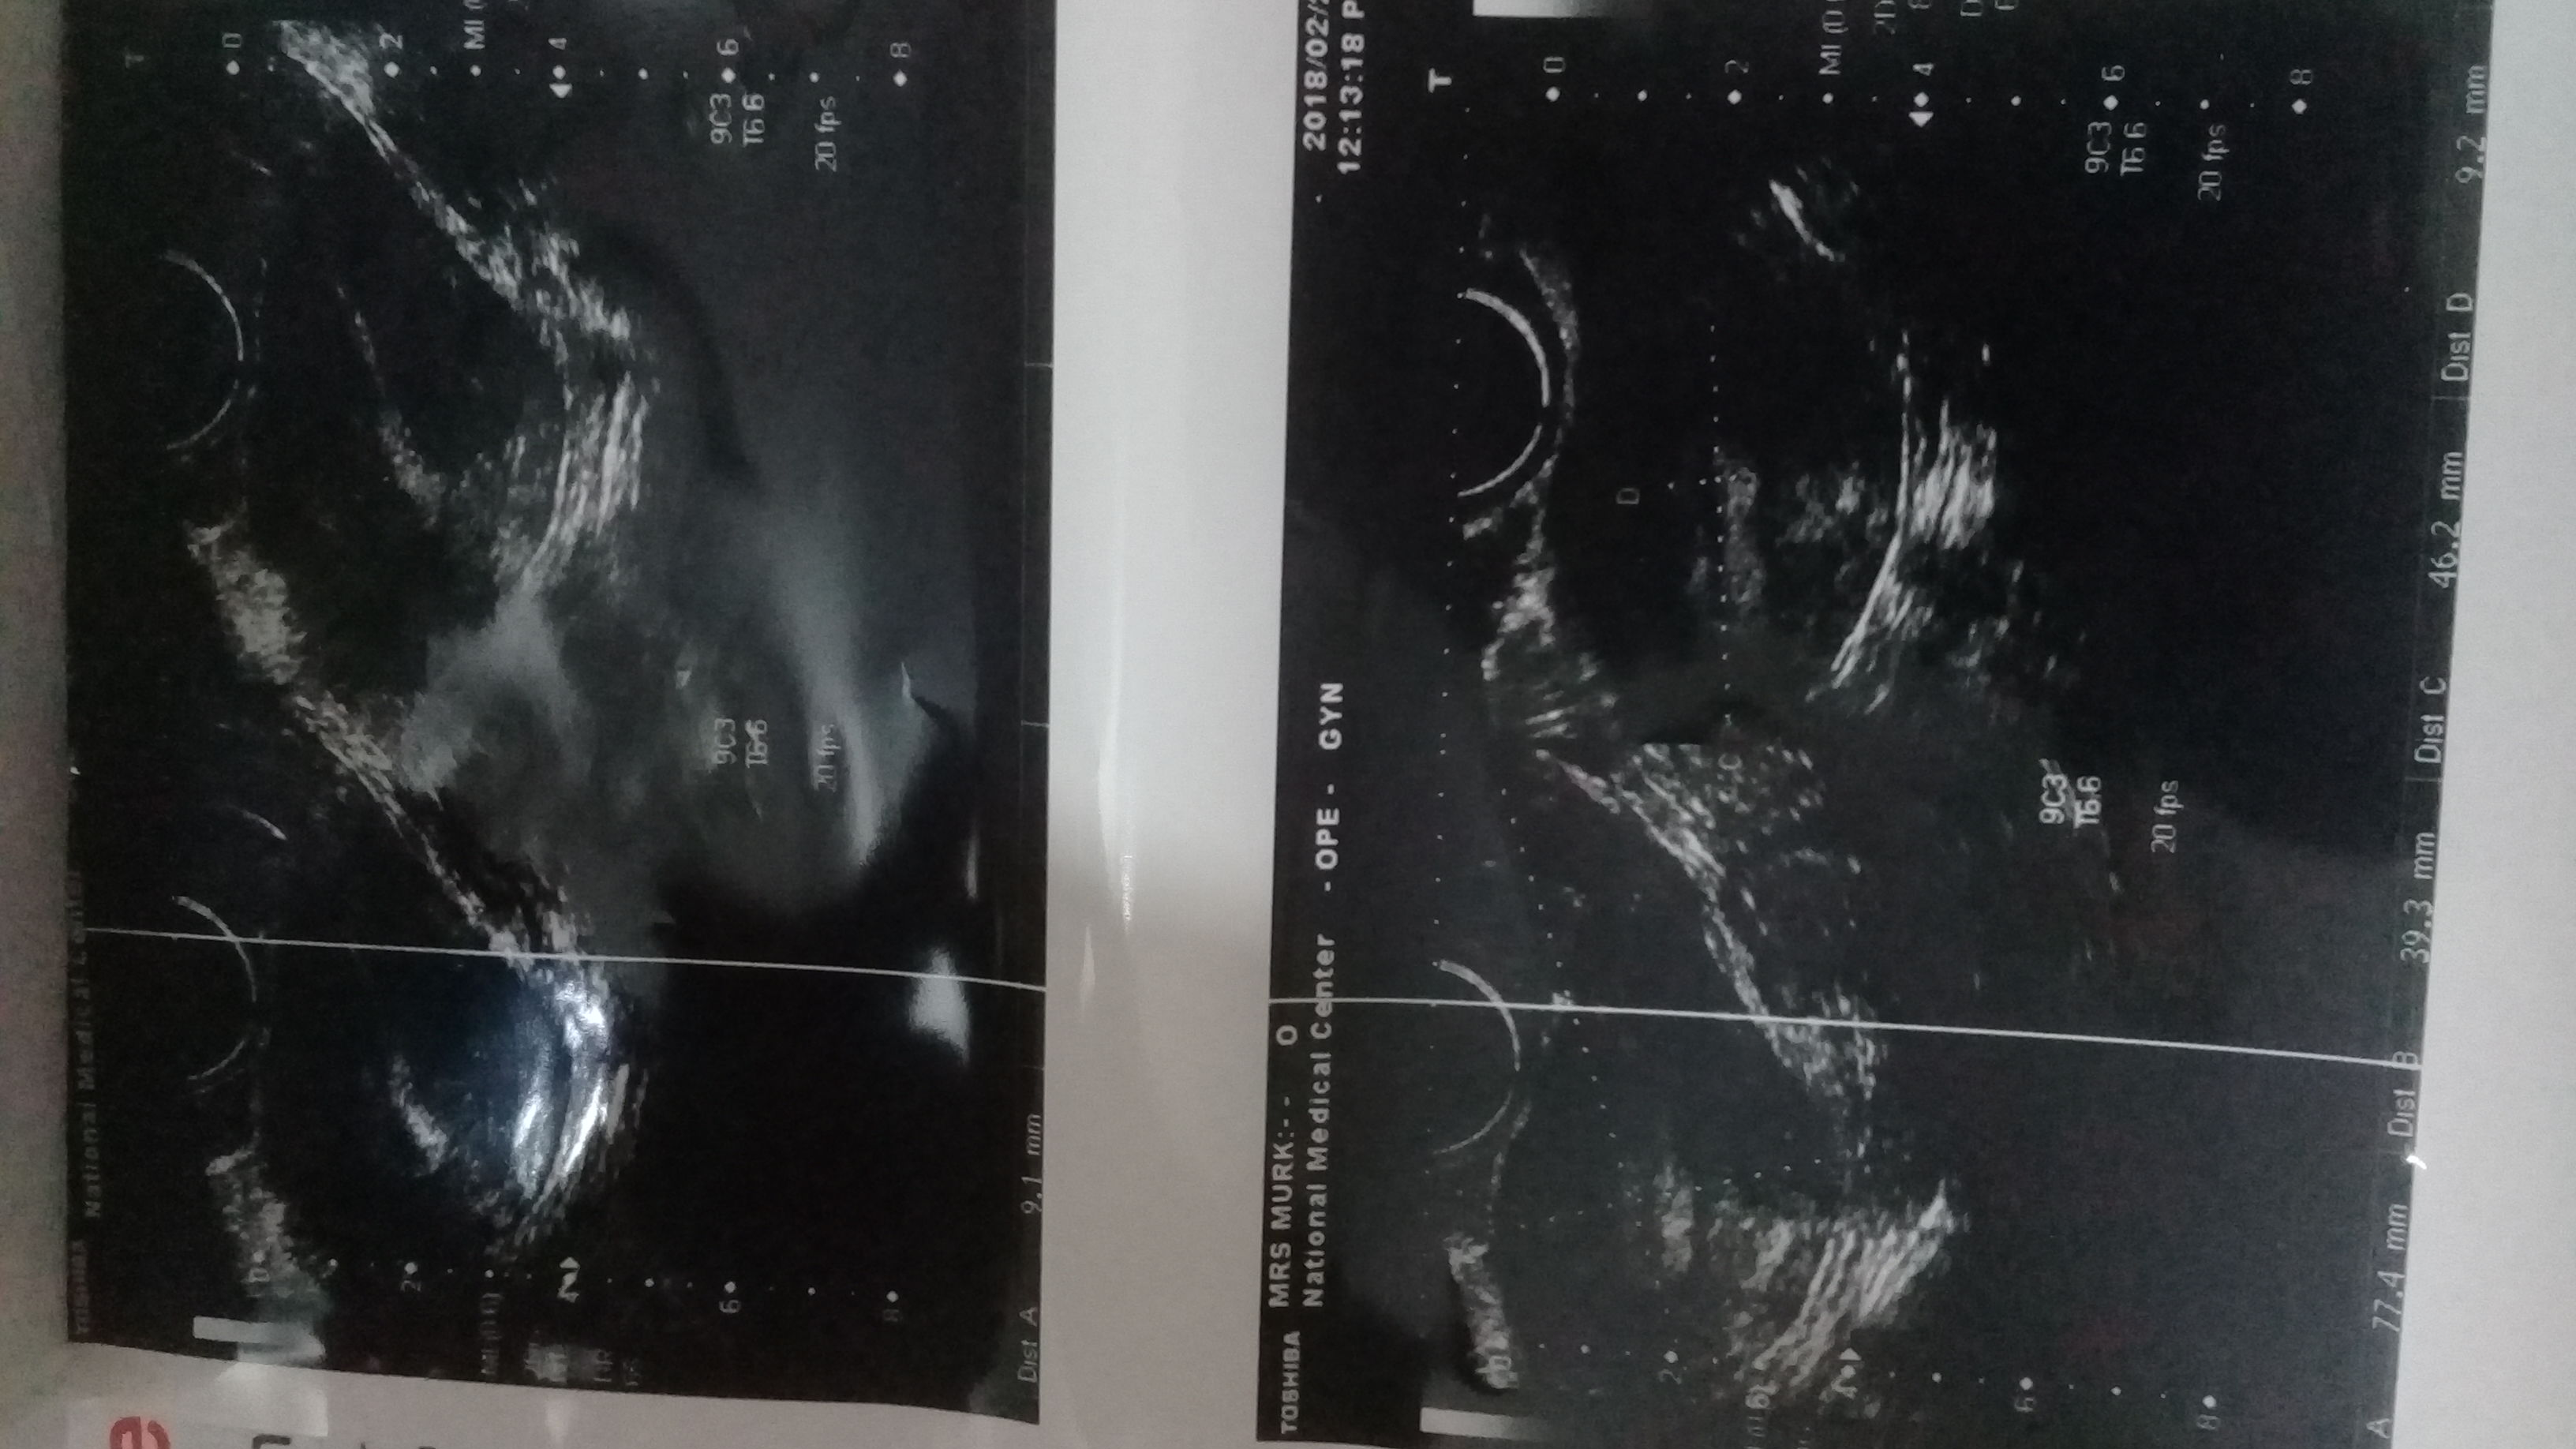

I have completed the coarse of vibramycin and flagyl for 7 days but still having throbbing pain have Ben to gyneacologist she said u have adhesions in pelvic area which makes more often infections again and again although this is first time experiencing such condition and she also suggest u have pco does my scan shows anything like this pls put light on it